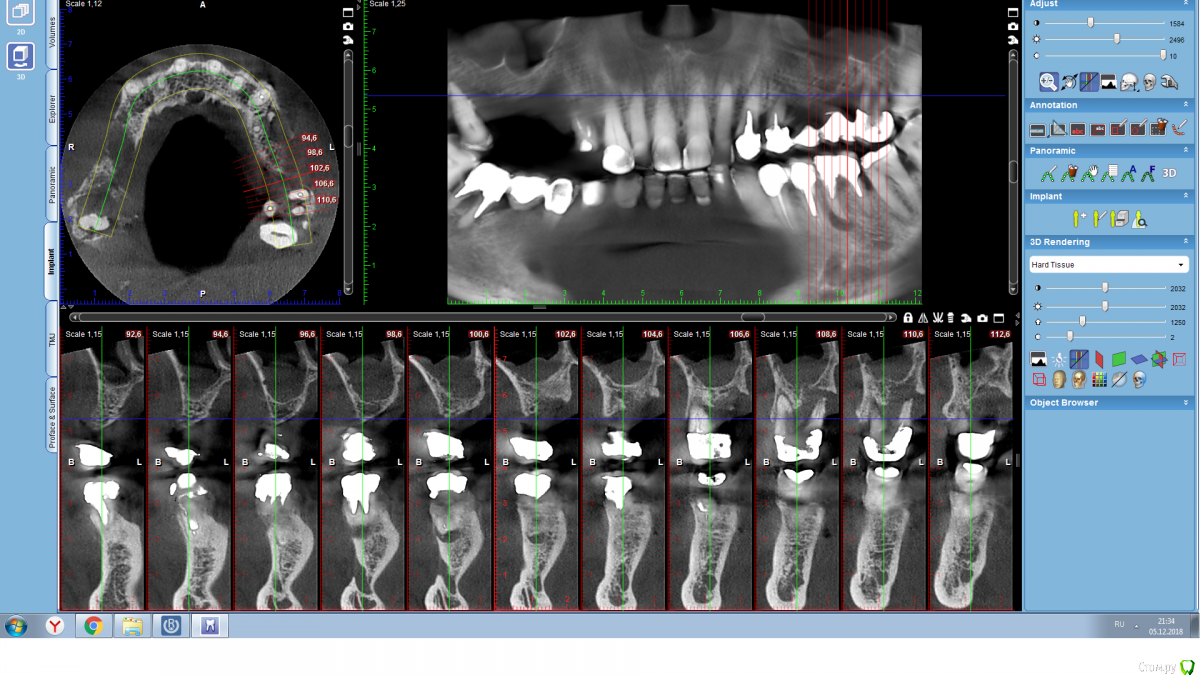

Serg2018 Опубликовано 28 ноября, 2018 Автор Поделиться Опубликовано 28 ноября, 2018 Вот пытаюсь выложить несколько срезов КТ правой стороны, надеюсь, я это правильно понял, делаю впервые. Также тыкал мышкой и она мне что-то замеряла, если в мм, то получается, что в самой тонкой части толщина 2,8 мм? или это я все неправильно понимаю? Ссылка на комментарий

Nazim_NV86 Опубликовано 28 ноября, 2018 Поделиться Опубликовано 28 ноября, 2018 (изменено) Sirona Galileos ?Должно быть окно, где срезы видны как распил. Сечение. Лучше на этом измерять. Можете всю томограмму загрузить на яндекс диск и выложить ссылку. Но сначала проверьте как работает запуск. На той программе, что выше написал, запуск скорее всего возможен только с диска. Если среди файлов на диске есть файл DCM, то его одного достаточно. Просмотрщик не нужно выкладывать. Изменено 28 ноября, 2018 пользователем Nazim_NV86 Ссылка на комментарий

Nazim_NV86 Опубликовано 29 ноября, 2018 Поделиться Опубликовано 29 ноября, 2018 (изменено) КЛКТ от 04.05.18г 8х8см. Что изменилось на сегодняшний день ? Какое то лечение/удаления было проведено с мая ? Тут не до шаблонов пока. Синусит двусторонний в том числе. Изменено 29 ноября, 2018 пользователем Nazim_NV86 Ссылка на комментарий